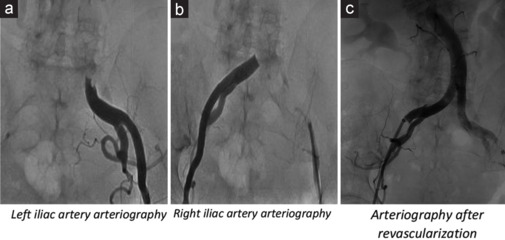

Left ventricular thrombosis (LVT) in stress cardiomyopathy or Takotsubo syndrome (TTS) is a moderately frequent complication. However, cardioembolic events are not frequently reported. Herein, we present a case report of 80-year-old patient admitted for chest pain at rest, started few days earlier following a violent argument. Her medical history included arterial hypertension and recent surgery of descending colon adenocarcinoma. Electrocardiogram showed sinus rhythm, negative T waves from V1 to V6, in D2, D3, AVF, and long QTc. Laboratory examinations documented an increased high sensitivity Troponin I, myoglobin, creatine kinase-MB, and B-type natriuretic peptide. Transthoracic echocardiography (TTE) showed a reduced left ventricular (LV) ejection fraction, "apical ballooning" with hyperkinesis of the basal segments of LV, suggestive for stress cardiomyopathy. A large thrombus in LV apex (3.3 cm × 2.1 cm) was found. Coronary angiogram showed normal coronary arteries. Anticoagulant therapy with Warfarin was quickly started, bridging with unfractionated heparin. Cardiac surgery was excluded for high-risk surgical patient. Daily TTE monitoring was done with evidence of slight reduction of the LVT. After 7th day from admission, the patient complained an intense and sudden pain in lower extremities bilaterally. An acute occlusion of the descending aorta just above the bifurcation in the common iliac arteries was found. Interventional radiology procedure of recanalization of the bis-iliac carrefour was successfully performed. However, few hours after the procedure, the patient's hemodynamic conditions worsened until the exitus.